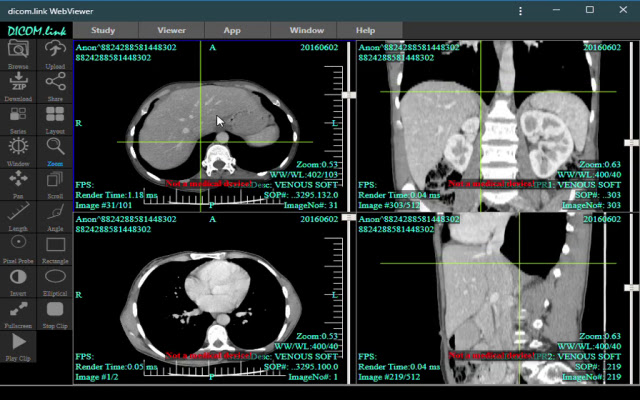

dicom.link Dicom Viewer in Chrome with OffiDocs

Advanced web-based DICOM Viewer for your local medical images or dicom.

link products.

dicom.

link DicomProxy frontend: can connect to your PACS and access images in web format.

Available feature: - dicomweb connectivity - WebRTC connectivity (using dicom.

link DicomProxy) to access your services behind firewall.

- drag and drop folders/files/zip archvies, including AES encrypted zips - save folder to zip archive - orthogonal MPR (not available in Lite viewer) - most viewing tools - most used transfer syntaxes - upload local images to your dicom.

link CloudPACS account or your standard PACS - secure and anonymous share your local files with other peers via WebRTC.

- dicom study anonymization (not available in Lite viewer) This is not a medical device.